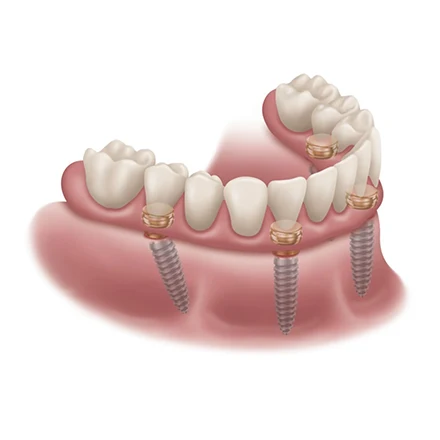

- Implant “Snap-In” Overdentures: Dentures that securely “snap” into 2–4 implants for ultimate confidence and stability.

- Fixed Dentures: The gold standard in tooth replacement; permanent teeth that don’t come out at night, offering the stability of natural teeth and a comfortable, palate-free design.